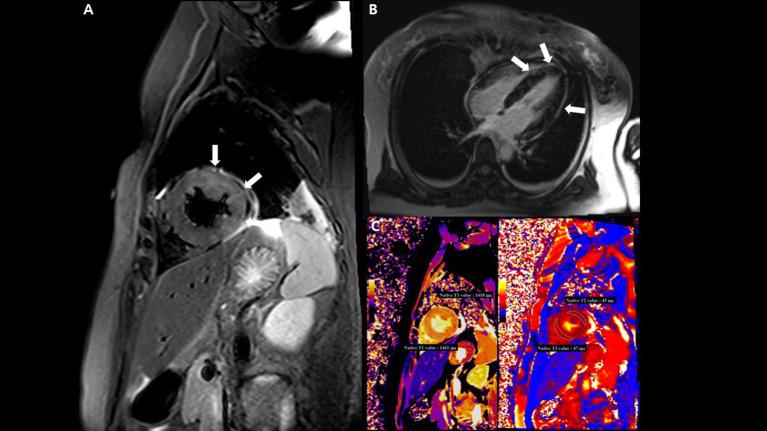

Case Report: Acute Fulminant Myocarditis and Cardiogenic Shock After Messenger RNA Coronavirus Disease 2019 Vaccination Requiring Extracorporeal Cardiopulmonary Resuscitation.

Recently, myocarditis following messenger RNA (mRNA) coronavirus disease 2019 (COVID-19) vaccination has become an important social issue worldwide. According to the reports so far, myocarditis related to mRNA COVID-19 vaccination is rare and usually associated with a benign clinical course without intensive care or any sequelae of fulminant myocarditis. Here, we report a case of acute fulminant myocarditis and cardiogenic shock after the mRNA COVID-19 vaccination, requiring extracorporeal cardiopulmonary resuscitation. Clinicians should keep in mind the possibility of progression to fulminant myocarditis in patients who presented with suggestive symptoms or signs of myocarditis after the COVID-19 vaccination.